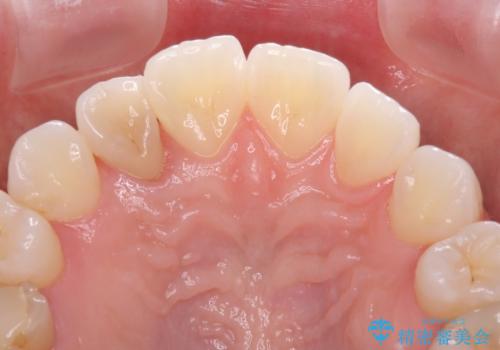

変色した前歯 オーダーメイドタイプのオールセラミッククラウン

- 虫歯により神経を取り除いた前歯の変色が気になるとのことで来院された患者様です。

レントゲン写真より、歯根の炎症が認められなかったため、ファイバーコアによる土台築製後、オーダーメイドタイプのオールセラミッククラウンにて補綴することとしました。